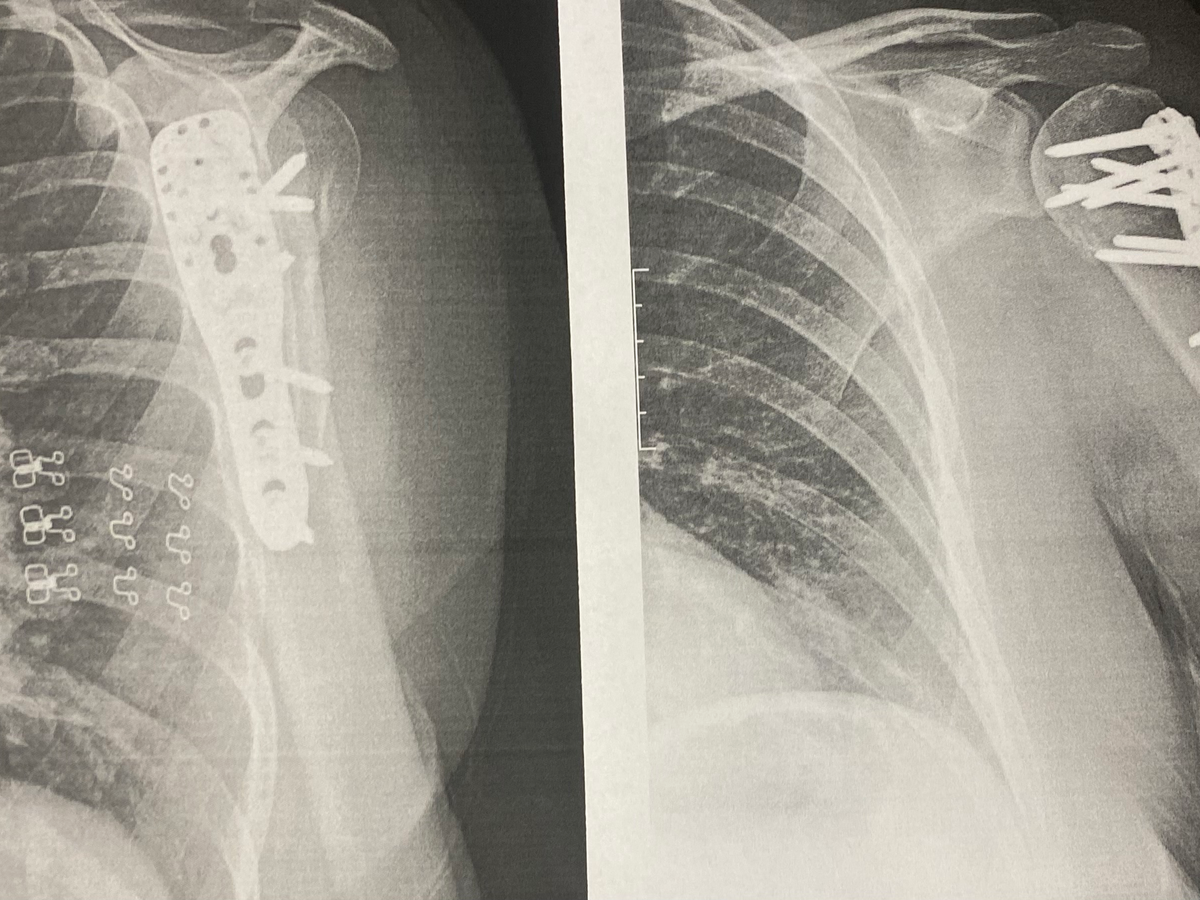

My name is Sharon Becker and I’m a recent victim of a hit and run. On March 3, 2025, I was riding an e-scooter in the bike lane of RR620 in Lakeway, Texas, when I was hit by a vehicle and separated from the scooter, resulting in a broken shoulder which will require surgery. Lakeway PD are investigating the identity of the driver who hit me and fled the scene. (Case # 25-00229 if you have information about this hit and run.)